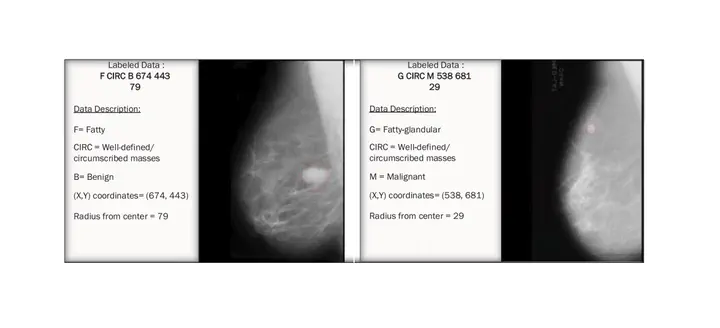

Embarking on my journey into the realm of breast cancer detection has been both challenging and enlightening. In my pursuit of advancing the field, I am particularly drawn to the development of self-supervised and unsupervised approaches for breast cancer detection.

The application of self-supervised learning techniques allows for using the inherent information within the data itself, minimizing the reliance on labeled datasets and opening up new possibilities for more efficient and generalizable detection models. Simultaneously, the exploration of unsupervised approaches promises to uncover hidden patterns and structures within the breast data, potentially revealing novel insights that could contribute to the improvement of early detection methods.